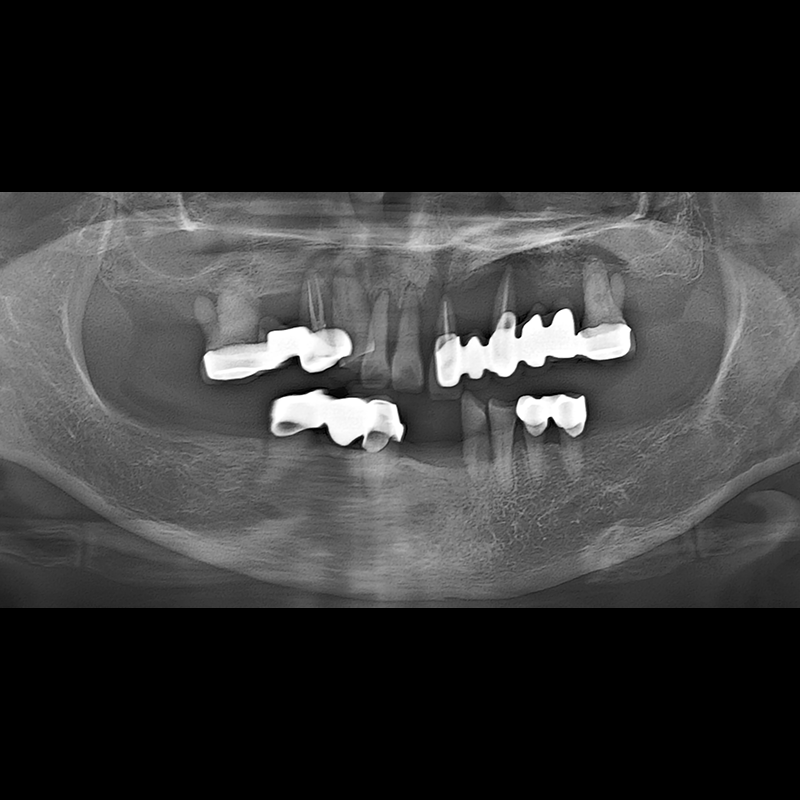

IMPLANT

BEFORE AFTER